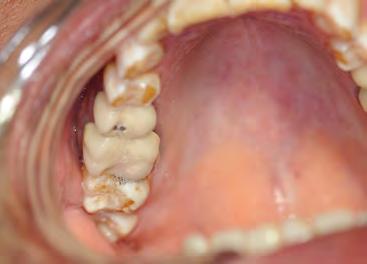

Two authors had access to the data and all information was de-identified. Study personnel made no contact with patients at any time throughout the study, and no PHI was recorded. Re corded data included diagnosis (clinical and/or pathologic), basic demographics (age, gender), and current prescription medica tions. For cases that were not biopsy-proven, the standard clinic protocol is that the clinical presentation must exhibit the charac teristic white Wickham striae for a patient to be given the clinical diagnosis of OLL or OLP (Figure 1). Any clinical diagnosis of OLL or OLP was rendered by one of four oral medicine experts in the Oral Medicine Clinic, and biopsy was performed in cases with any doubt.

Figure 1. Example of characteristic Wickham striae and reticular pattern on buccal mucosa used to clinically diagnose OLL and OLP cases. Erythematous areas also seen. Figure 2. Frequency and percent of study patients using specific medications with color-coded drug classes.